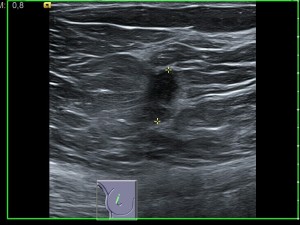

La ecografìa es el metodo diagnostico de eleccior para estudiar la mama de mujeres menores de 35 años (que tienen mucho parénquima), pero se utiliza tambien despues de la mamografia si no podemos hacer un diagnostico final.